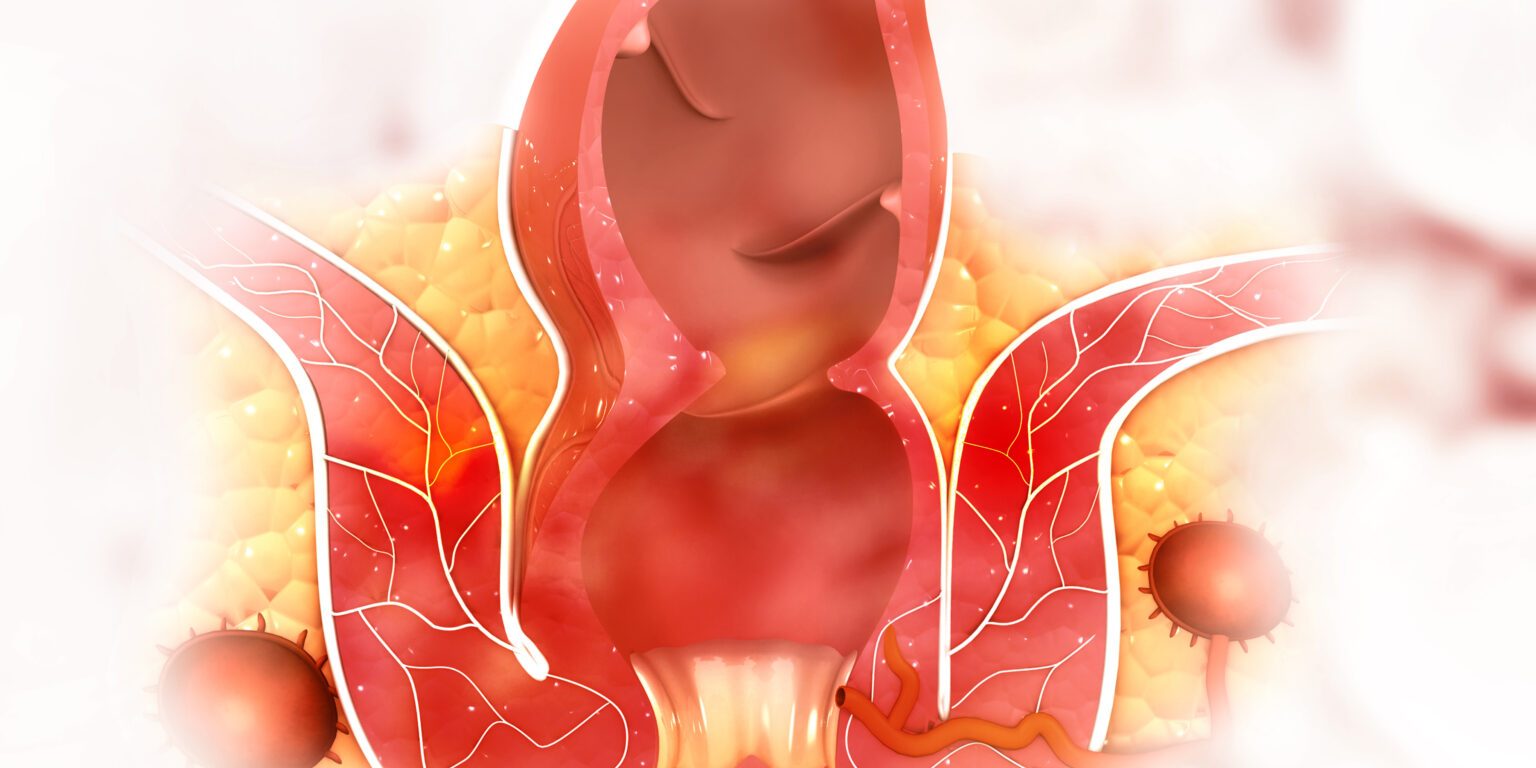

Οι αιμορροΐδες είναι πρησμένες φλέβες που αναπτύσσονται γύρω από τον πρωκτό. Όταν εμφανιστούν, μπορούν να προκαλέσουν πόνο και αιμορραγία. Οποιοσδήποτε μπορεί να αναπτύξει αιμορροΐδες, αλλά οι έγκυες γυναίκες διατρέχουν μεγαλύτερο κίνδυνο.

Οι γιατροί χωρίζουν τις αιμορροΐδες σε δύο διαφορετικούς τύπους – εσωτερικές και εξωτερικές αιμορροΐδες.

αιμορροΐδες – 3d ιατρικό μοντέλο